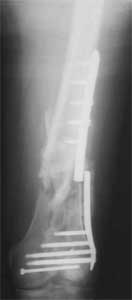

I presented a series of ~25 such cases at EuroTrauma'2004. Many cases were discussed here. I attach am example. Look also recent cases at http://www.hwbf.org/hwb/conf/alex58/scfx.htm,

http://www.hwbf.org/hwb/conf/alex63/alex63.htm

- Your last posted case: how is possible to have secure fixation with applied construct without additional casting, bracing or Ilizarov?

At that moment we had in stock only the 10 mm solid nails so of course there was no idea about early weight bearing. But it was quite enough for early knee ROM excersises (see attached). Two locking screws through the distal block provided that.